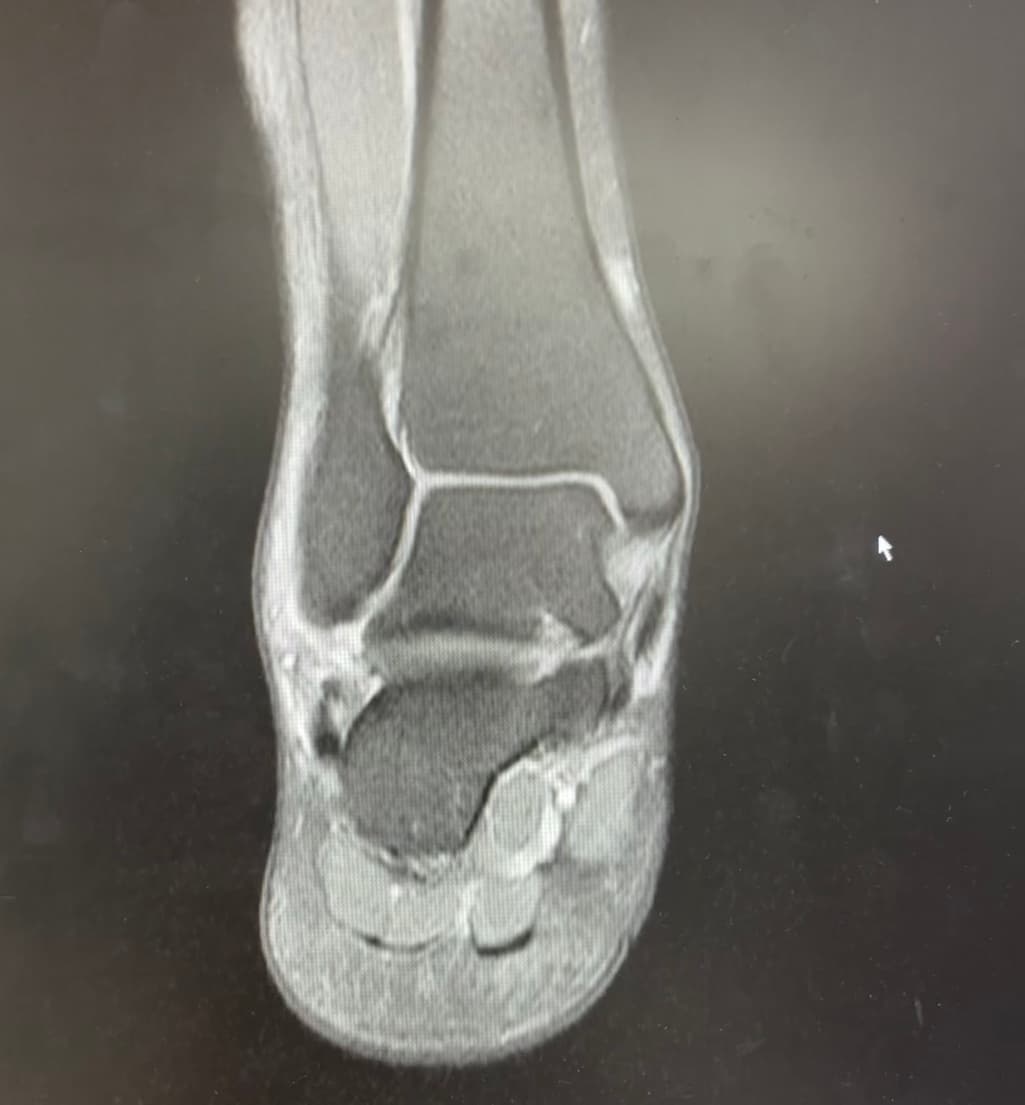

종비인대 전거비 인대 부분 파열 소견이 있는데

종비인대와 전거비 인대 파열로 인한 불안정성은 재활을 통해 개선될 수 있지만 완전한 회복 여부는 개인의 상태와 재활 과정에 따라 다릅니다. 수술을 고려할 경우 인대 이식이 필요할 수 있고 이는 재발 위험을 줄이는 데 도움이 될 수 있습니다. 정상적인 활동으로 돌아갈 가능성은 있지만 평생 조심하며 관리하는 것이 필요할 수도 있습니다!